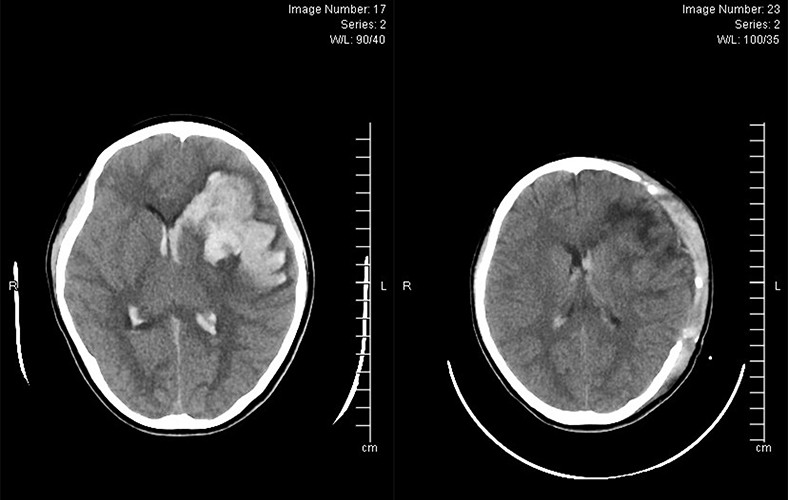

1 giờ trước khi nhập viện, bệnh nhi Nguyễn L.Q.N, (13 tuổi, trú tại TP Hạ Long, Quảng Ninh) có tình trạng co giật, giảm ý thức. Cấp cứu tại Bệnh viện Bãi Cháy, N. được thăm khám lâm sàng, cận lâm sàng, kết quả chụp Ctscaner sọ não cho thấy hình ảnh xuất huyết não.

Các bác sĩ đã hội chẩn, kết luận bệnh nhân xuất huyết não do vỡ khối thông động tĩnh mạch não (AVM). Tiên lượng tình trạng bệnh nhân nặng, nguy cơ tử vong cao, các bác sĩ đã tiến hành phẫu thuật mở sọ cắt bỏ khối dị dạng AVM, giải áp, lấy máu tụ.